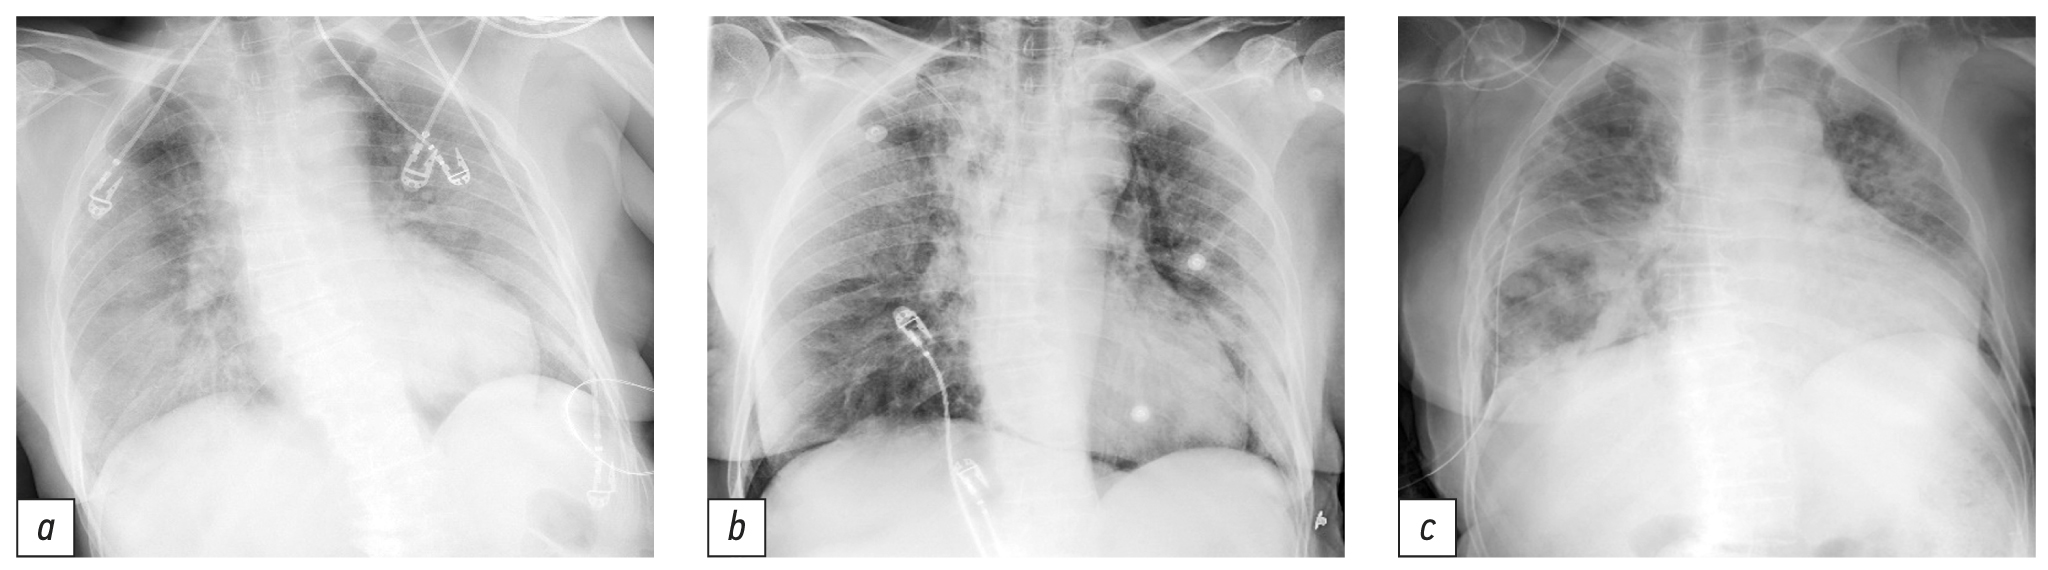

На третий день госпитализации в связи с появлением гнойной мокроты, нарастанием одышки, увеличением площади инфильтрации лёгочной ткани при рентгенографии (рис. 1, а), снижением SpO2 до 90% к лечению добавлены цефтриаксон (с 15.09 по 20.09.2021) с последующей заменой на линезолид и меропенем (с 28.09 по 07.10.2021), ремдесивир (с 17.09 по 26.09.2021), олокизумаб и левилимаб (16.09.2012 однократно), высокопоточная оксигенация, противогрибковая терапия (флуконазол с 30.09 по 12.10.2021).

Рис. 1. Рентгенография лёгких (цифровая, прямая задняя проекция): а ― 9-е сут болезни (обширные субплевральные участки снижения пневматизации обоих лёгких с нечёткими контурами, средней и низкой плотности ― двусторонняя интерстициальная пневмония); b ― 15-е сут болезни (положительная динамика в виде уменьшения интенсивности инфильтрации лёгочной ткани над обоими лёгочными полями); с ― 27-е сут болезни (справа в нижних отделах визуализируется негомогенный участок просветления 60×74 мм с толстыми стенками).

05.10.2021 после кратковременной положительной динамики в виде уменьшения инфильтрации лёгочной ткани по результатам рентгенографии (см. рис. 1, b) и субъективного улучшения самочувствия вновь отмечались ухудшение состояния, нарастание одышки, появление упорного кашля с обильной гнойной мокротой, снижение сатурации до 94% на фоне оксигенотерапии, аускультативно сопровождающееся влажными хрипами над всей поверхностью лёгких. КТ-картина (от 05.10.2021) двусторонней полисегментарной пневмонии смешанной этологии ― вирусной (COVID-19, КТ-4) и бактериальной, с признаками деструкции в нижней доле правого лёгкого, правостороннего гидропневмоторакса, пневмомедиастинума, подкожной и межмышечной эмфиземы шеи.

16.10.2021 по результатам КТ и рентгенографии сохранялись признаки правостороннего гидропневмоторакса, деструкции в нижней доле правого лёгкого (см. рис. 1, с). Выполнено дренирование правой плевральной полости (16.10.2021).